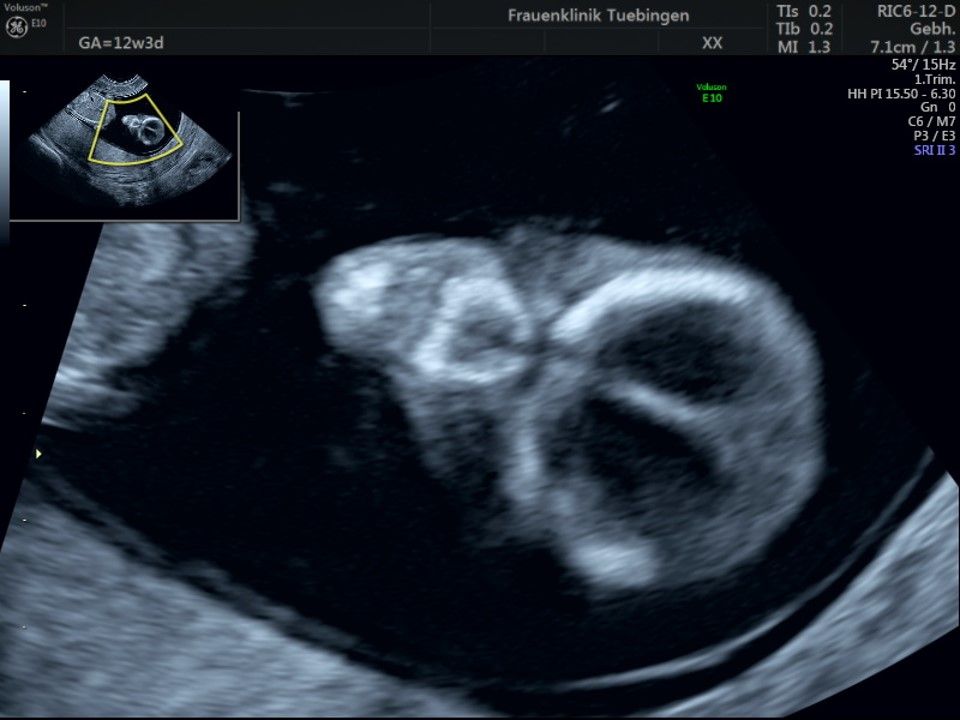

Im Rahmen des Ersttrimester-Screenings untersuchen wir die Organe des Feten mittels Ultraschall. Dabei machen wir auch gerne ein Bild für Sie.

Obwohl der Fet zu diesem Zeitpunkt erst zwischen 5 und 8cm groß ist, lassen sich bereits etwa die Hälfte aller schwerwiegenden Fehlbildungen erkennen bzw. ausschließen. Sollten wir eine Auffälligkeit sehen, werden wir mit Ihnen den Befund und das weitere Vorgehen ausführlich besprechen.

Die eigentliche Organuntersuchung findet um die 20.SSW (zweites Screening) statt. Das Ersttrimester-Screening und das zweite Screening sind sich ergänzende Untersuchungen und ersetzen sich gegenseitig nicht.

Das Ergebnis der Ultraschalluntersuchung ist wegweisend. Dabei wird der Fet vermessen, die Organe werden untersucht und die sonographischen Marker zur Risikoberechnung für Chromosomenstörungen werden beurteilt. Das sind: die Nackentransparenzdicke, Nasenbein sowie der Blutfluss in der rechten Herzhälfte und im Ductus venosus, einem Gefäß in der Leber des Feten.